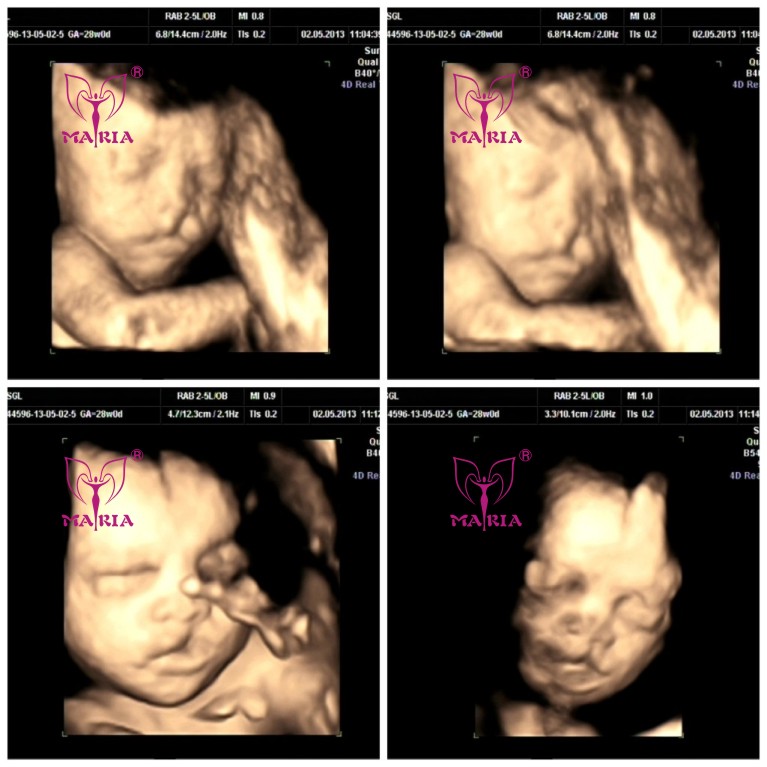

专家建议准爸准妈选择怀孕23-27周照四维彩超能有效检查出宝宝身体是否存在缺陷,此时四维彩超可以立体照出宝宝全身,能清晰地看到宝宝的形态,通过观察宝宝某个部位来判断宝宝是否存在外在缺陷。

三维和四维蕞大的区别在于多了一个"时间维",前者是静止的,后者是动态的。也就是说,三维彩超是图片,四维彩超是录像,彩超医生能够从不同角度显示更多的细节,所以有助于诊断像唇裂那样的问题,从而帮助医生提早计划宝宝出生后的补救措施;而三维彩超只能看到宫内胎儿局部立体图像,如果是胎儿的面部羊水较多则看的清楚,如果其他部位羊水少则很难看清了,不仅检查耗时长,而且排畸不到位。

另外,高清彩超设备的应用,也让孕妈们能够更清楚的看到宝宝模样。E8四维彩超让刻盘留念更有价值,不管是给亲朋好友分享,孕友间的比较都jue对是先进的画质,孩子长大以后再看都不会影响效果。即使E8四维彩超比三维彩超稍贵一些,也jue对是物超所值的。

杭州玛莉亚妇产医院是目前还引进了国际上蕞为尖端的四维彩超设备--E8高层次四维彩超。E8更出彩的地方,就是能进行早期妊娠颈后透明带(NT)进行自动检测,降低人为误差,减少唐氏综合症的风险值。E8高层次四维彩超的这一独特功能,就是上一代四维彩超所无法触及的技术优势。